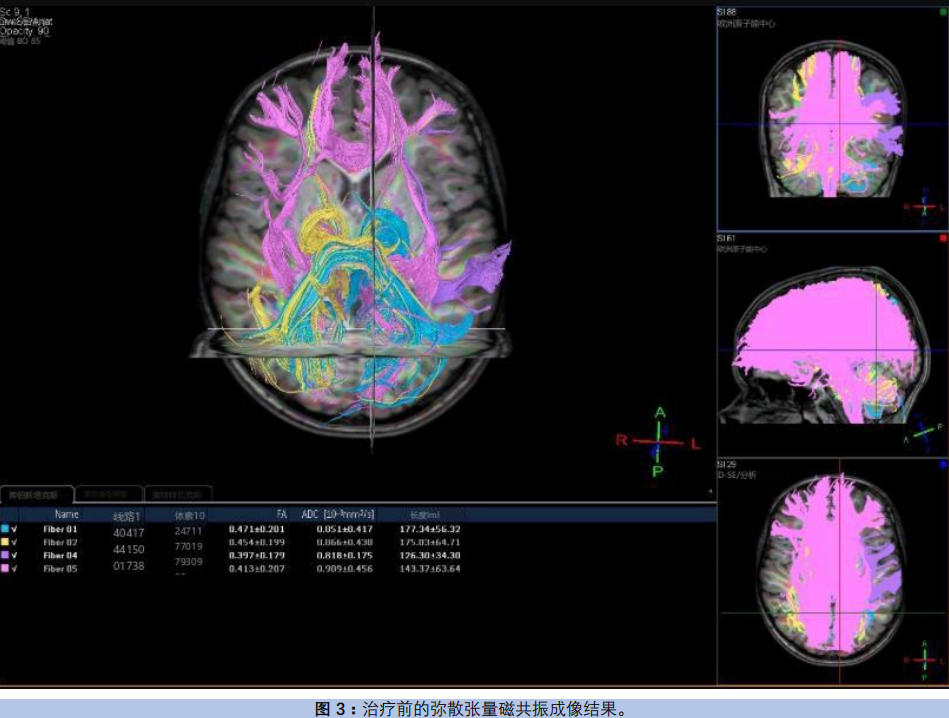

弥散张量磁共振成像显示(图3),胼胝体联络纤维各向异性分数(FA)值0.413±0.207,韦尼克区与布罗卡区弓状束FA值0.397±0.179,低于正常对照,提示语言相关神经环路连接受损。同时检出左侧颞极蛛网膜囊肿与不完全性海马倒置。